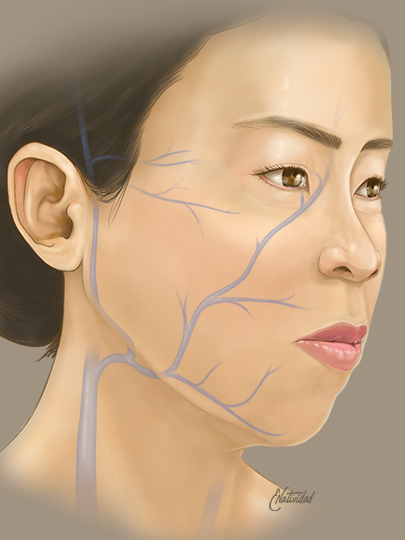

Running series of animated visual abstracts, Quick Takes, created for The New England Journal of Medicine as part of a team of illustrators, medical writers, and scientists. These short, iconographic animations aim to succinctly describe clinical trials and increase the awareness and understanding of important research findings.

Adopting The Journal’s visual style and asset library, I am responsible for the entire production process including narration editing, storyboarding, layout, illustration, and animation.